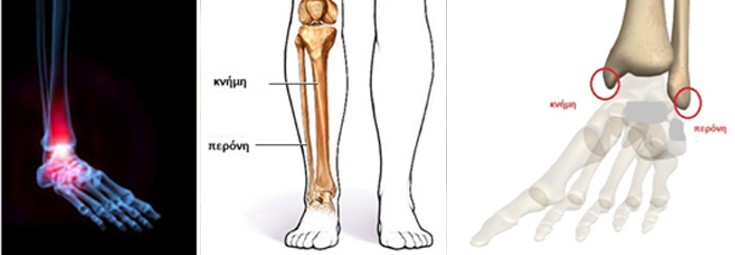

Τα κατάγματα αυτά αφορούν τους δύο «αστραγάλους», τον έξω και τον έσω, οι οποίοι στην πραγματικότητα είναι οι άκρες των δύο οστών, της κνήμης και της περόνης, τα οποία συγκρατούν με την άρθρωση της ποδοκνημικής τον αστράγαλο, όπως μεταφέρεται το βάρος του σώματος στη βάδιση.

Τι είναι